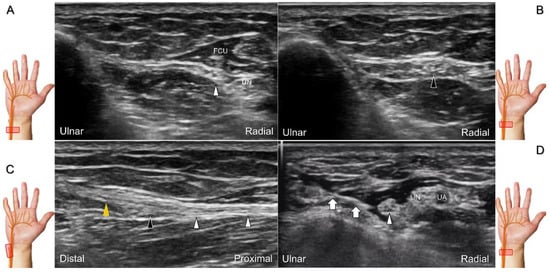

Figure 20. Sonographic tracking (short-axis view) of the dorsal ulnar cutaneous nerve from its normal (A) to the swollen segment (B) proximal to the entrapment. The normal, swollen, and entrapped segments of the dorsal ulnar cutaneous nerve are seen in long-axis imaging (C). Ultrasound-guided hydrodissection of the nerve (D). White arrowheads: normal segment; black arrowheads: swollen segment; orange arrowhead: entrapped segment; white arrows: needle. FCU: flexor carpi ulnaris muscle; UN: ulnar nerve; UA: ulnar artery.

With the forearm in supination, the transducer is placed on the distal third of the ventral forearm to locate the myotendinous junction of the FCU. The dorsal ulnar cutaneous nerve branches from the ulnar aspect of the ulnar nerve underneath the FCU, and then wraps around the distal ulna to reach the dorsal wrist. Moving the transducer to the dorsal wrist, the nerve can be seen coursing above the extensor carpi ulnaris tendon (Figure 19), toward the dorsal ulnar wrist and hand region.

Clinical Implication

The causes of damage/entrapment of the dorsal ulnar cutaneous nerve include compression over the distal forearm by a bracelet or a metal implant, extensor carpi ulnaris tenosynovitis, or triangular fibrocartilage complex injury [43]. For hydrodissection of the entrapped nerve (Figure 20A–C), the in-plane approach targeting its short axis is preferred (Figure 20D).